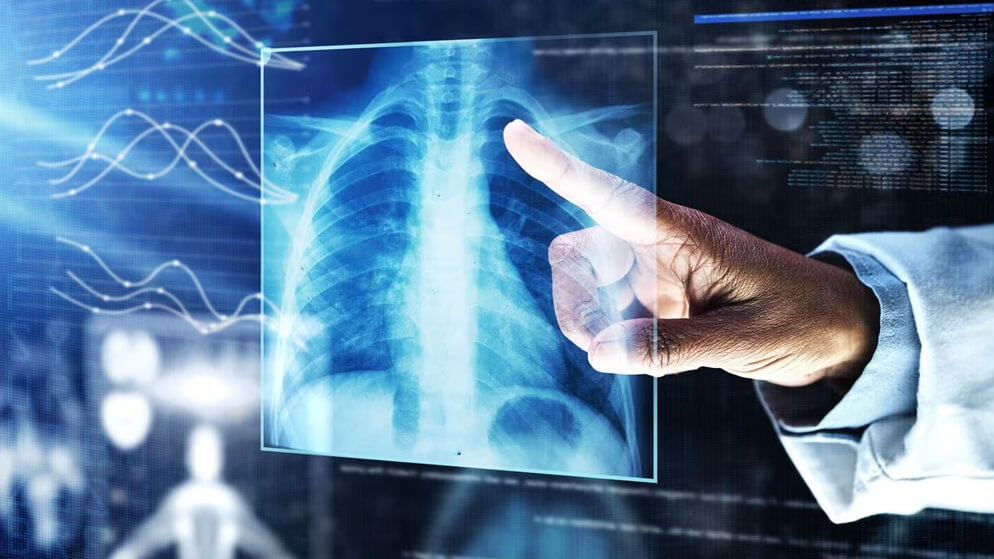

Living in Dubai, the vibrant hub of the Middle East, can be exhilarating. But amidst the hustle and bustle, respiratory issues and allergies can take a toll on your well-being. Whether you’re struggling with persistent lung problems, battling seasonal allergies, or suspecting an allergic reaction, finding the right specialist is crucial.

• Pulmonologist: Focuses on respiratory conditions like asthma, COPD, lung infections, and sleep apnea.